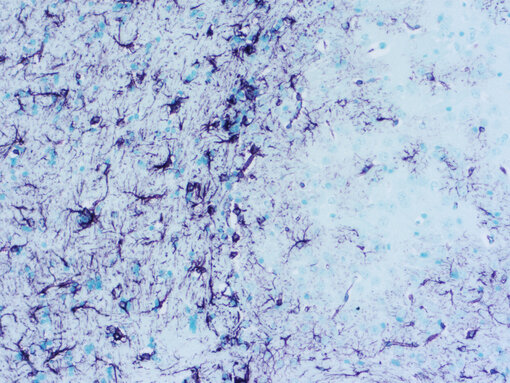

GFAP staining using  VIP in mouse brain

Figure 1: Chromogenic detection using ImmPACT VIP (purple) as HRP substrate. Counterstain: methylene green (light green).